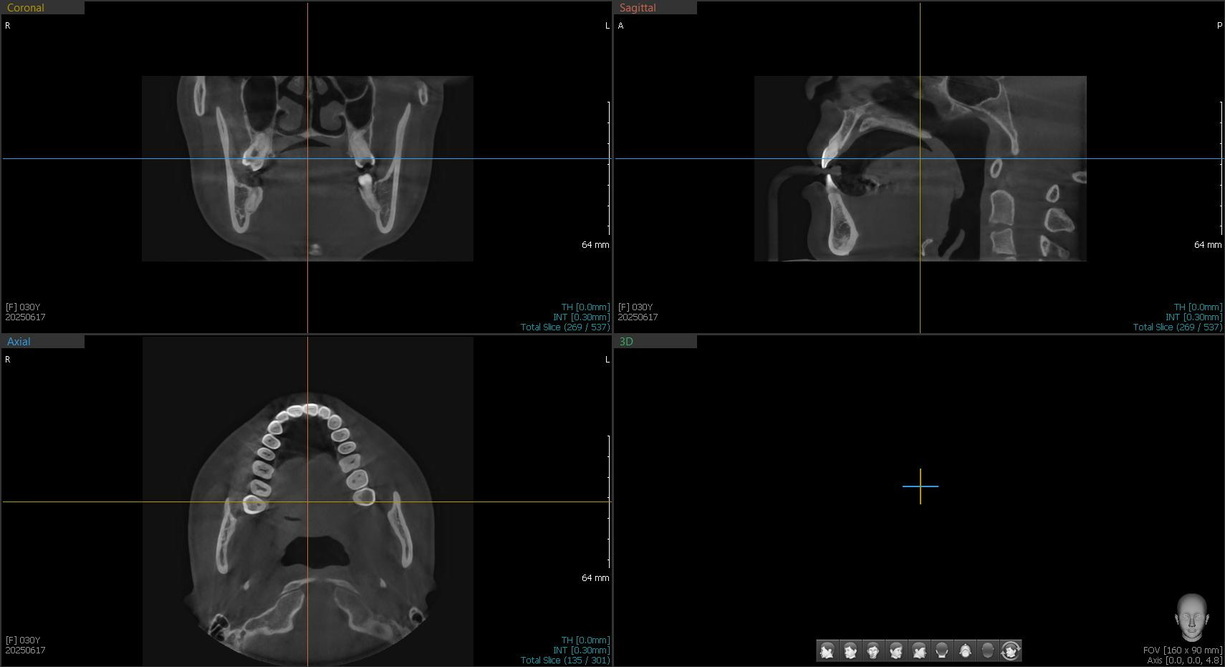

КТ в стоматологии — это продвинутое рентгенологическое исследование зубов, челюстей и суставов. Его проводят с помощью конусно-лучевого томографа. В отличие от обычного рентген-аппарата он выдает высокоточные объемные цифровые снимки. Врач может приблизить изображение, повернуть нужной стороной и рассмотреть челюстно-лицевую область пациента максимально подробно.

Компьютерные 3D-исследования обязательно назначают перед имплантацией зубов. Полученные снимки важны для качественной работы ортопеда и челюстно-лицевого хирурга. Врачи оценивают состояние и толщину челюстей, чтобы понимать, какой протокол лечения больше подойдет пациенту. Снимки томографа помогают определить, на какую глубину вкручивать имплант и под каким углом. Детальный реалистичный снимок КТ зубов и челюстей позволяет планировать операцию без рисков задеть гайморовы пазухи и нижнечелюстной нерв.

Пациент заходит в рентген-кабинет, врач помогает ему надеть просвинцованный фартук, чтобы защитить от излучения ткани, которые не нужны для исследования. Дальше голову пациента фиксируют в томографе с помощью специальных опор. Лучи направляют строго в места, информация о которых нужна лечащему врачу. Датчик вращается вокруг головы человека, выполняя около 150-200 двухмерных снимков высокого разрешения за один круг. Полученные изображения компьютер преобразует в 3D-формат.